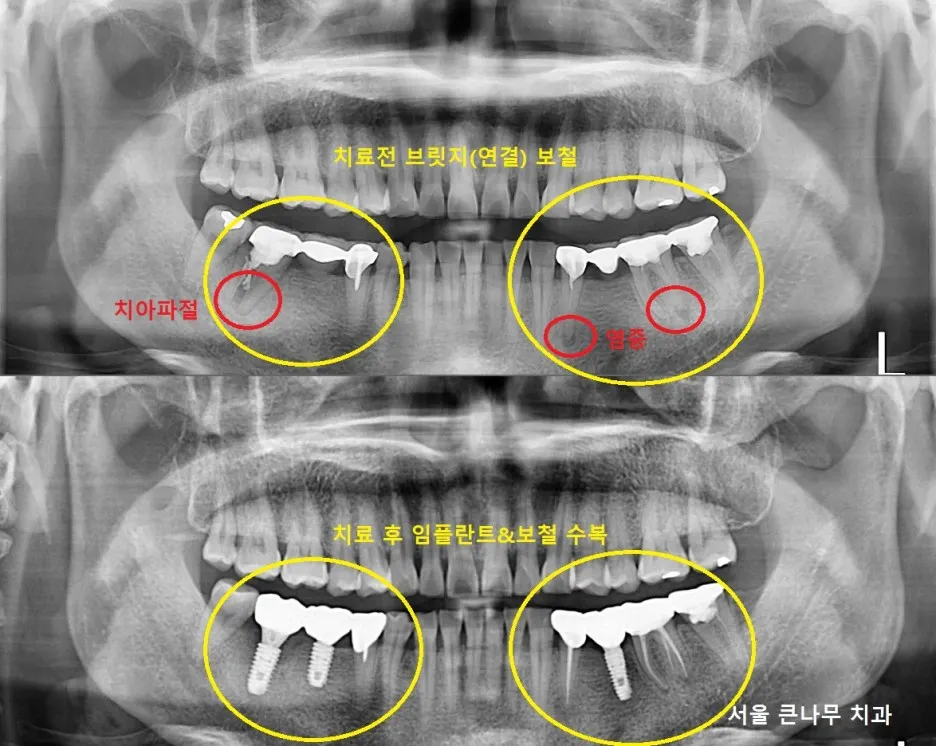

서울큰나무치과에 방문해 주신 50대 여성분입니다.

환자분께서는 4개 치아로 이어져있던 브릿지 중 왼쪽 뿌리 끝에 염증이 발견되었습니다. 이로 인해 브릿지 제거 후 비어있는 공간에 임플란트 를 하나 식립하였습니다. 또한, 뿌리 끝 염증이 있는 2개 치아는 재신경치료 후 지르코니아 크라운 으로 다시 수복해주었습니다.

1년이 지난 지금은 뿌리끝 염증이 많이 사라진 상태입니다.

반대쪽인 오른쪽도 비슷한 상황이라서 몇달 후에 다시 내원하셨습니다.

오른쪽 큰 어금니는 뿌리가 파절되어 있어 발치를 진행하게 되었습니다.

3개로 연결되어 있던 브릿지 보철 제거가 이루어졌고, 이와 함께 발치 후 당일 즉시식립으로 임플란트를 바로 심어주었고 뼈이식도 함께 해주었습니다. 작은 어금니는 지르코니아 크라운으로 다시 수복해주었습니다.

양쪽 모두 3달 정도의 기간이 지난 후 모든 치료가 완료가 되었습니다.